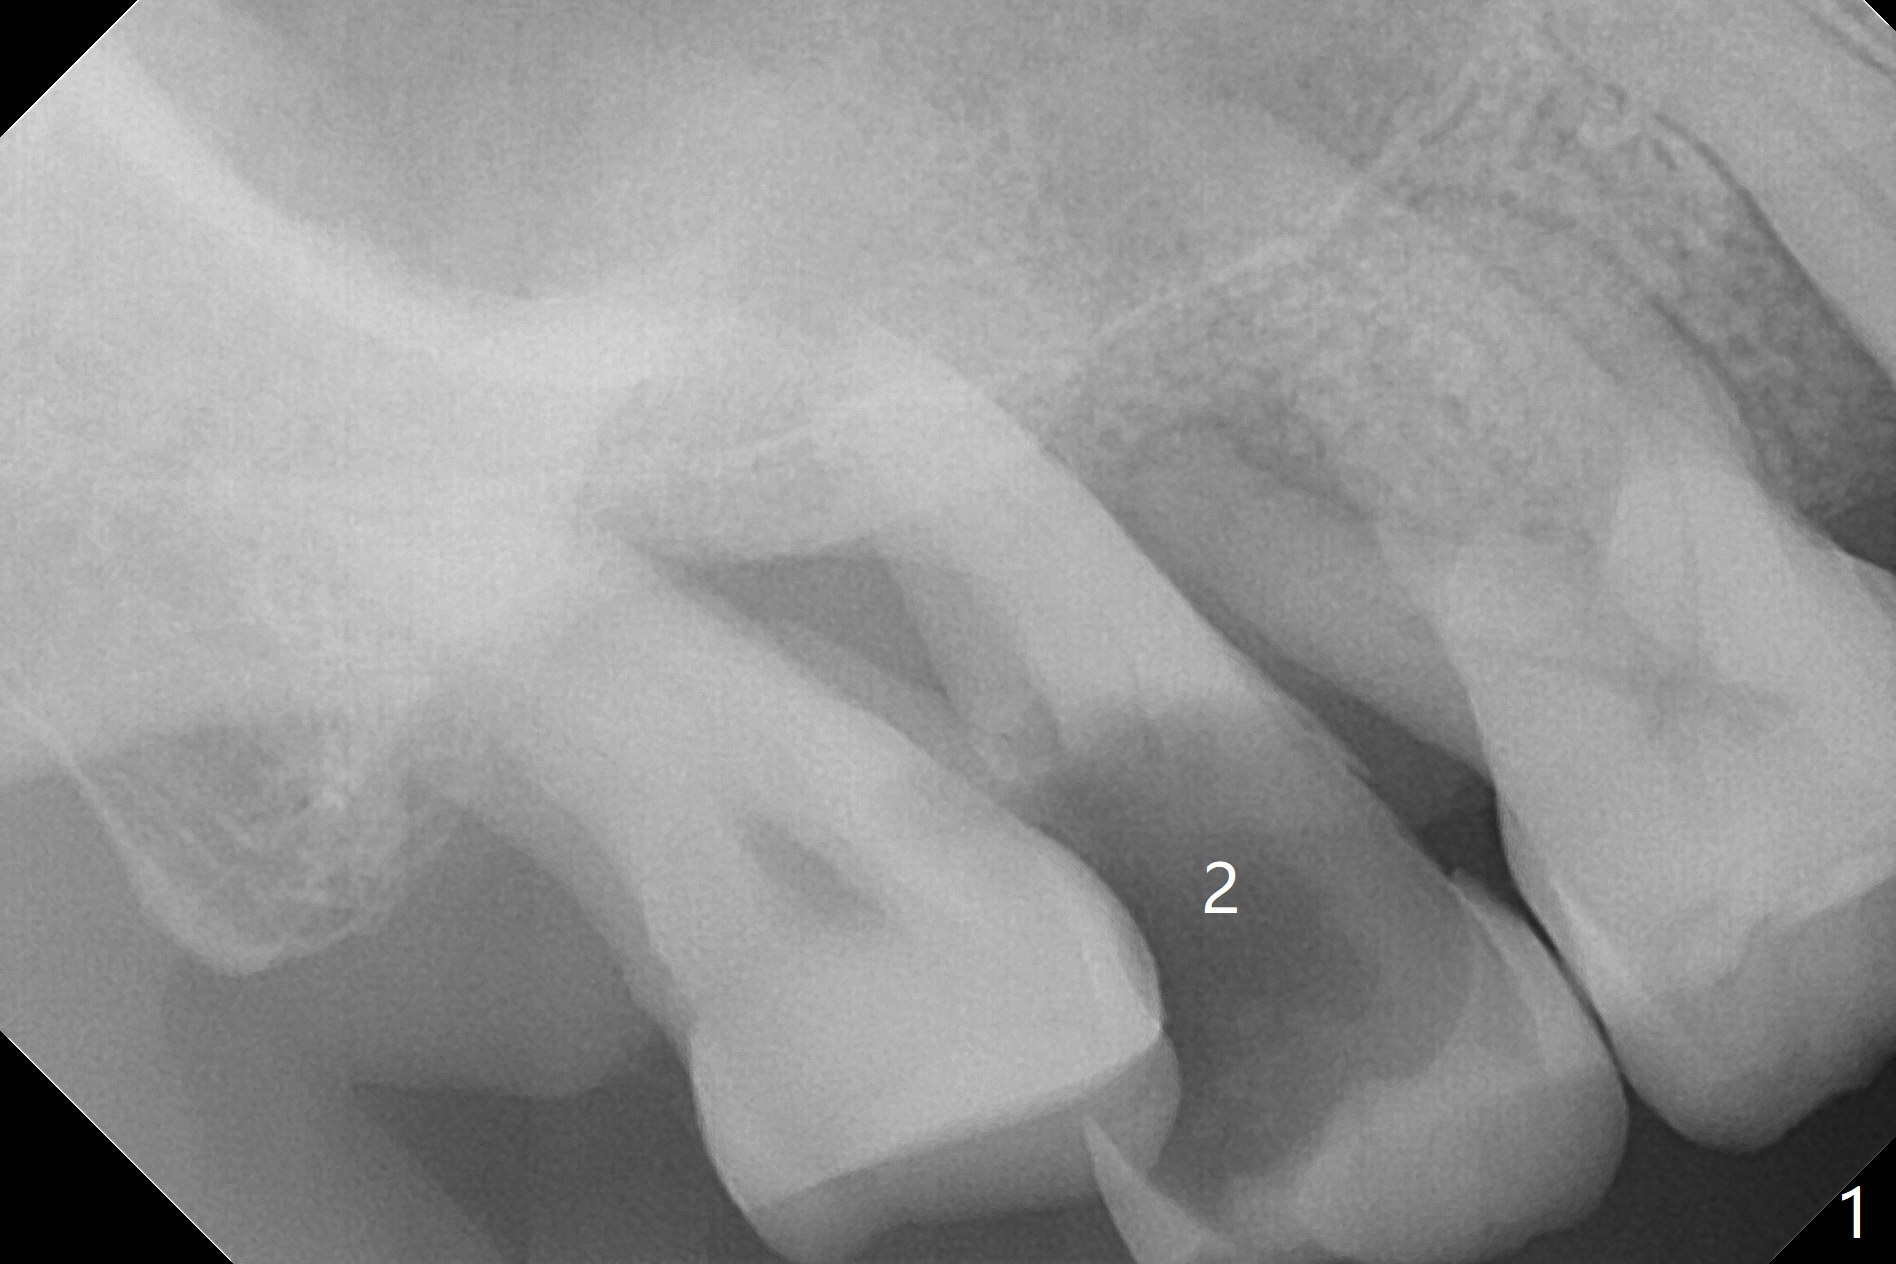

A 66-year-old man has moderate to severe chronic periodontitis. After scaling & root planing, he will return for #2 and 13 residual root removal (Fig.1,2). The latter will be done in the traditional non-sterile manner except Chlorhexidine mouth rinse and Iodine application as usual. After curettage with serrated curette, irrigation and 2x2 gauze, all of used instruments will be sent to sterilization room. A set of new instruments will be used with sterile towel spreading and sterile gloves. The strict sterile procedure is applied to sinus lift to prevent infection as this case, since the bone height is limited (Fig.2 IS). PRF and sticky bone will be carried out as well. Antibiotic Study will be terminated from now on. Take 12x9 preop CT after discussion. Prepare DIO Sinus Kit.